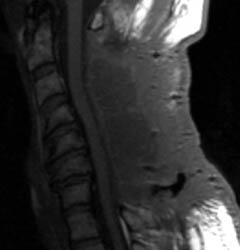

46 y.o.  male, initial complaint of progressed with myelopathy, difficulty walking, and imbalance. Underwent laminectomy C3 to C7, 2 months prior to these images. Worsening numbness and weakness brought patient to seek neurosurgical consultation again, prompting repeat imaging.

Sagittal T1 pre (A) and post contrast (B),  sagittal T2 (C) and Axial T1 post contrast (D) MRI images of the cervical spine demonstrating a large posterior fluid collection with an obvious sinus tract inferiorly and associated gas bubbles. This was proved to be a post-operative seroma and epidural scar (note the thick rind of enhancement) that was partially accounting for this patient's residual and worsening symptoms despite the initial decompressive surgery.